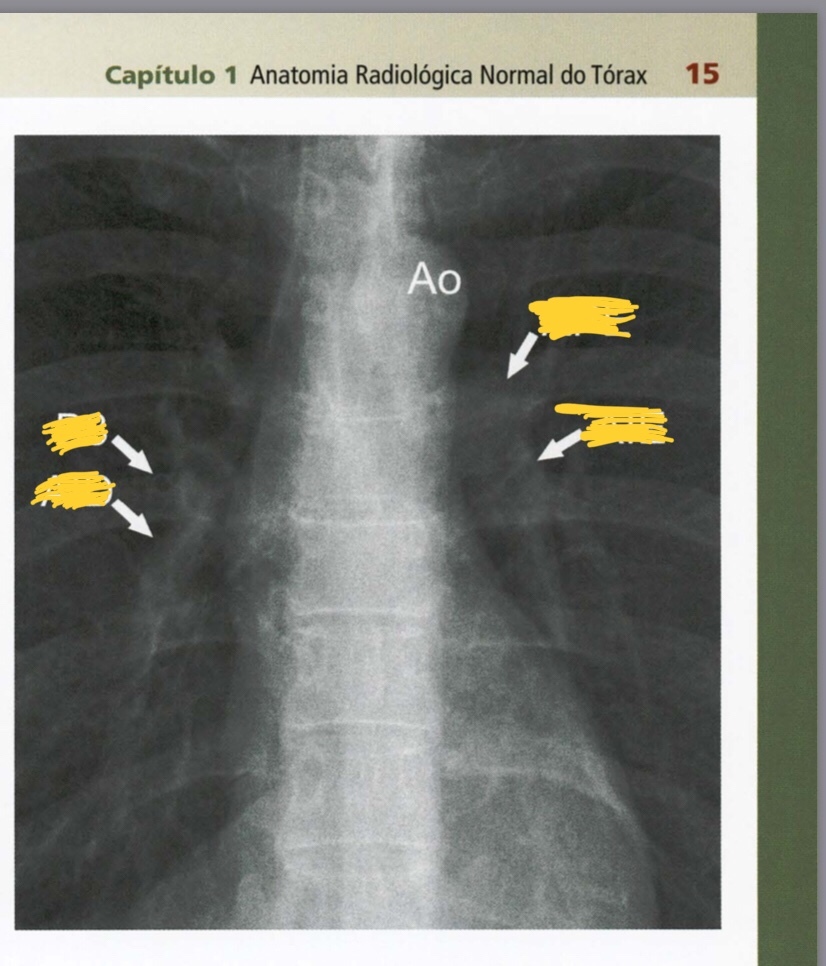

Quais são as estruturas apontadas?